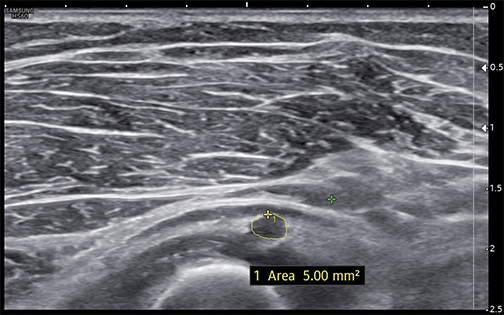

Measured short-axis ultrasound image of the deep motor branch of the radial nerve at the arcade of Frohse showing a cross-sectional area of approximately 5.0 mm² (normal <3.0 mm²).